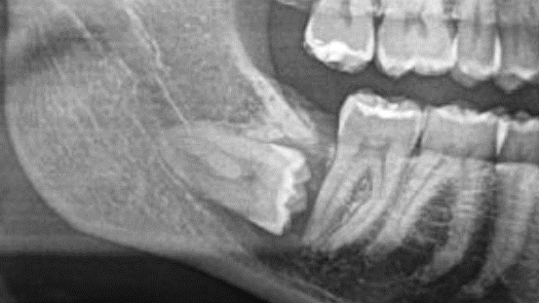

Notwendig werden solche Eingriffe häufig durch verlagerte Zähne, zum Beispiel Weisheitszähne, Zysten in den Kieferhöhlen und gutartige Tumoren des Zahnhalteapparats und des Kieferknochens. Die Operationen werden insbesondere dann bei uns durchgeführt, wenn sie aufgrund eines erhöhten Schwierigkeitsgrades nicht in einer zahnärztlichen Praxis realisierbar sind. Darüber hinaus bieten wir eine spezialisierte Betreuung für Patientinnen und Patienten mit Allgemeinerkrankungen und erhöhten Risikoprofilen, die eine intensivere Überwachung während und nach der Operation erfordern.

In direkter Nachbarschaft des Kiefers verlaufen wichtige Strukturen wie etwa Nerven und Gefäße. Um das Risiko einer Verletzung und die Ausdehnung der Operation so gering wie möglich zu halten, empfehlen wir in bestimmten Fällen vor dem Eingriff eine 3D-Röntgendiagnostik, bekannt als Digitale Volumentomographie (DVT). Diese Art der Bildgebung wird jedoch von den gesetzlichen Krankenkassen in der Regel nicht übernommen.

Als Alternative besteht die Möglichkeit, notwendige Schnittbildgebungen (MRT oder CT) in einer niedergelassenen radiologischen Praxis durchführen zu lassen. Dies kann nach einer Überweisung durch Ihre Hausärztin oder Ihren Hausarzt erfolgen. Der dabei erstellte Bilddatensatz kann dann zur Vorbesprechung mitgebracht werden, um die Operation optimal zu planen und durchzuführen.